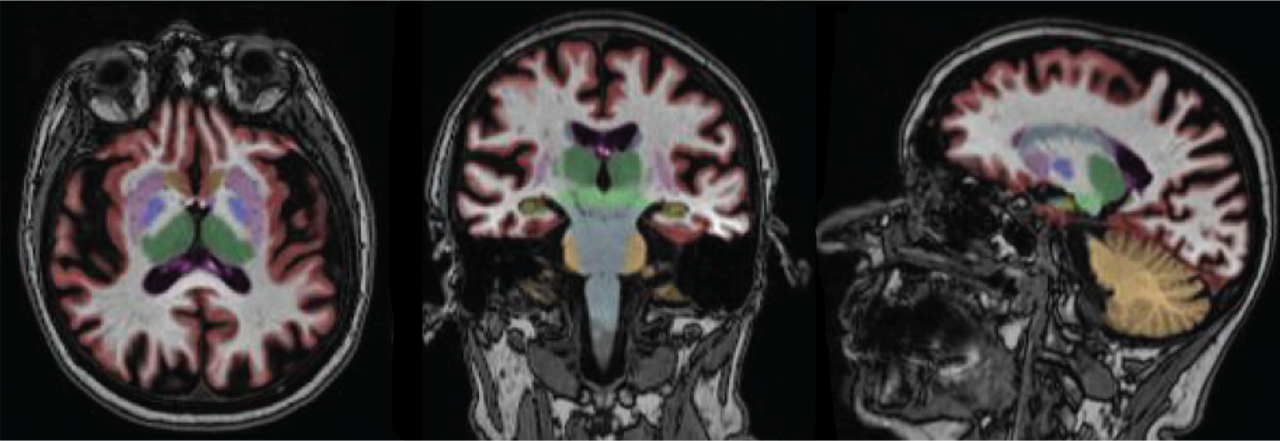

Neuroquant est un logiciel de post traitement 3D permettant aux radiologues de fournir à leur correspondant une évaluation quantitative du volume des structures cérébrales.

NEUROQUANT segmente et mesure le volume des hippocampes, des ventricules, des noyaux gris et de nombreuses autres structures cérébrales et compare le volume obtenu à celui d’une population de référence de même âge et de même sexe. Cette information permet une meilleure évaluation de l’impact de pathologies neurodégénératives ou neurologiques sur la morphologie du cerveau.

Le manipulateur réalisant l’acquisition envoie les données sur un serveur sécurisé ou NEUROQUANT identifie et segmente automatiquement les différentes structures cérébrales.

Le logiciel NEUROQUANT fournit plusieurs rapports permettant une évaluation visuelle et quantitative.